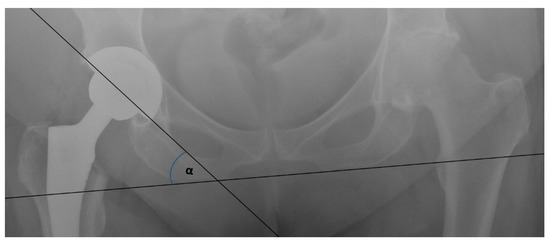

3.3. Mean Radiographic Cup Inclination

| Nistor [8], 2017 DAA vs. LA | 36.97° (SD 1.85°) | 39.63° (SD 2.88°) | ||

| Reichert [21], 2018 DAA vs. LA | 38.6° (SD 5.7°) | 40.3° (SD 6.2°) | ||

| Dienstknecht [22], 2014 DAA vs. LA | 48.1° (SD 6.0°) | 49.7° (SD 6.0°) | ||

| Cheng [23], 2017 DAA vs. PA | 46.07° | 45.86° | ||

| Taunton [24], 2014 DAA vs. PA | 38.0° | 40.0° | ||

| Barret [25], 2013 DAA vs. PLA | 47.1° (SD 6.1°) | 42.4° (SD 7.6°) | ||

| Zhao [26], 2017 DAA vs. PLA | 41.3° | 40.8° | ||

| Taunton [27], 2018 DAA vs. PA | 37° (SD 5°) | 39° (SD 6°) | ||

| Brun [28],2019 DAA vs. LA | 49.5° (SD 7.4°) | 47.0° (SD 6.0°) |